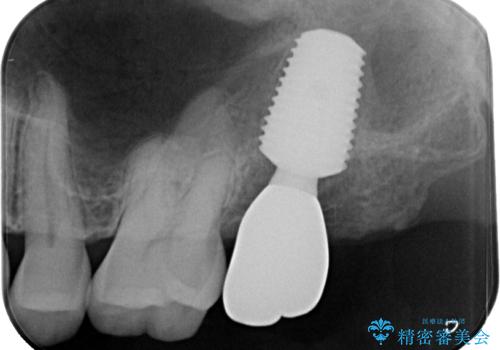

インプラントの埋入から被せものの装着まで2ヶ月で終えることができました。治療期間も短く、しっかり咬めるため大変喜んでいただきました。